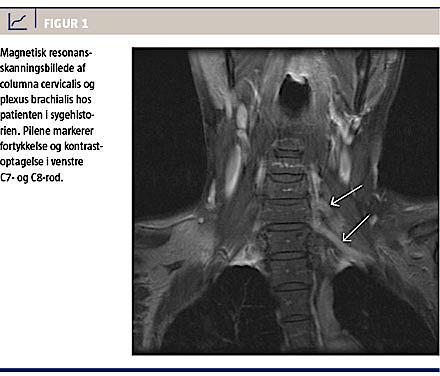

undersøgelse seks måneder senere viste kombineret motorisk og sensorisk affektion af n. ulnaris sin. og forlænget F-wave-latens i begge nerver, hvilket er foreneligt med påvirkning af den nedre del af plexus brachialis. Der blev udført magnetisk resonans

(MR)-skanning af columna cervicalis og plexus brachialis med et halvt års interval; først ved den tredje

skanning blev der påvist en let fortykkelse og kontrastoptagelse i venstre C7- og C8-rod (Figur 1). Gentagelse af positronemissionstomografi (PET)-computertomografi (CT), der tidligere havde vist normale forhold, viste nu opladning i tilsvarende region, som MR-skanningen gjorde. To spinalvæskeprøver var negative for tumorceller.